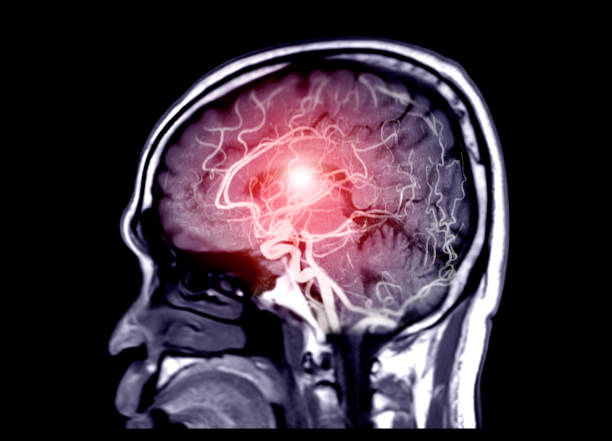

뇌동맥류 증상 자세히 알아보기

뇌동맥류는 뇌의 혈관이 벽의 약한 부분이나 손상으로 인해 팽창하거나 부풀어 오른 상태를 말합니다. 뇌동맥류는 일반적으로 증상이 없으며, 우연히 발견되기도 합니다. 그러나 뇌동맥류가 크거나 위치가 민감한 경우, 심각한 증상을 초래할 수 있어 이번 시간에는 뇌동맥류로 나타나는 증상에 대해 자세히 알아보도록 하겠습니다.